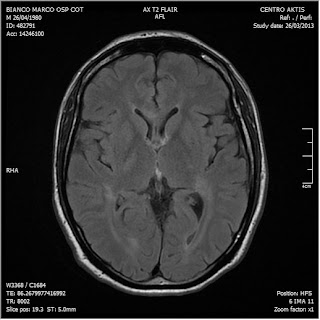

26/03/2013. Ritorna a controllo al Cotugno dove effettua nuova RM con MdC

RM del 26/3/2013